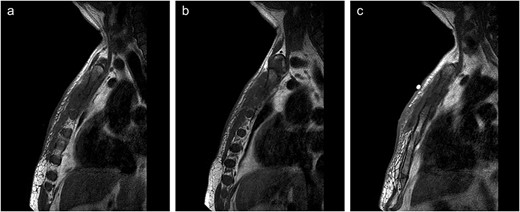

He then presented 3 weeks later referred by his general practitioner (GP) to the surgical hot clinic with worsening swellings of the sternum and discharge from the inferior aspect of the sternum. He had been given oral flucloxacillin by the GP, but was clinically well and not septic. Physical observations were within normal limits. On examination, there was a 3 × 3 cm swelling overlying the body of the sternum with discharge. Superior to that was another diffuse inflammatory swelling. Blood tests revealed CRP of 86, his LFTs had returned to normal and FBC was normal. Options were considered as to whether to drain under lupus anticoagulant, but given the recent computed tomogramphy (CT) chest showing possible pectoral involvement, the decision was made to admit to hospital for incision and drainage under GA. He was consented as such and admitted. He was then reviewed the next day by the on call consultant surgeon, who felt given the prolonged history of the swelling that an abscess was unlikely. Magnetic resonance imaging (MRI) of the sternum was, therefore, recommended by the radiologists to further characterize the lesion (Fig. 1a–c). MRI of the area revealed fluid within the manubriosternal joint with erosion of the articular margins. A fluid collection 65 × 7 mm was presented within the right pectoralis major, along with a small collection in the medial aspect of left pectoralis major. Also present was surrounding soft tissue thickening and oedema with marrow oedema of the upper body of sternum and manubriosternal joint. No abnormality was demonstrated in the underlying mediastinum. The MRI concluded that this was septic arthritis of the manubriosternal joint with bony erosion and underlying osteomyelitis.

(a–c) Lateral views of sternal MRI showing varying degrees of inflammation and septic arthritis of manubriosternal joint.